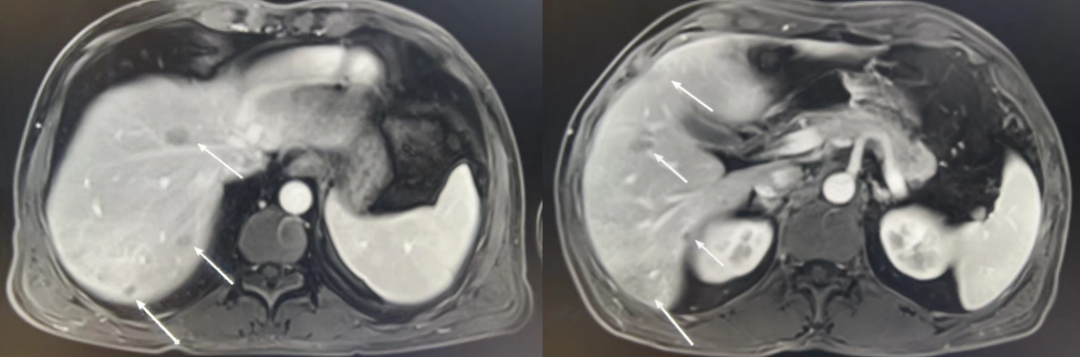

在全球,结直肠癌是发病率位居第三位、病死率位居第二位的肿瘤。肠镜筛查的普及以及手术方式的提升显著降低了结直肠癌的死亡率,但仍有一部分患者在初诊时已发展为晚期,失去手术根治的机会,且预后较差,5年生存率仅12%。许多转移性结直肠癌(mCRC)患者在经历一线治疗后,面临无药可用的困境。近年来,随着靶免联合治疗在系统治疗中逐渐前移,各种靶向治疗药物在mCRC的诊疗中也越发举足轻重。本文分享2例晚期结肠癌患者的诊疗经过,呈现瑞戈非尼在二线治疗为患者带来长生存的治疗价值及其良好的后线应用前景,以期为临床医生提供诊疗借鉴。 病例提供:海军军医大学附属长征医院 王湛 王湛 病例基本情况 一般信息:女 ,58岁。2020年10月,患者无明显诱因出现腹胀,无伴随症状,未予重视。后腹胀进行性加重,2020年11月中旬下腹部隐痛,与进食及体位变化无关,无肩背部放射痛。 辅助检查: 腹部超声:腹腔积液。 腹水脱落细胞病理:腺癌。 腹部增强CT:结肠肝曲癌;腹盆腔积液,腹盆腔腹膜多发转移。 结肠镜(2020-12-4):升结肠近肝曲见隆起型新生物,范围约4cm,新生物表面分叶状,质脆,触之易出血。肠腔狭窄,内镜尚可通过。 2020-12-8病理:横结肠,中分化腺癌,含部分粘液腺癌。 一线治疗2020-12-03至2021-02-24 CAPEOX+贝伐珠单抗 治疗4周期 病情进展,腹胀、腹痛加重,腹水增加。 2021-3-31 PET-CT:腹腔内及腹膜、脾脏、纵隔及右侧心膈角区、左侧锁骨区多发代谢增高灶,结合病史,考虑转移;双肺转移;腹腔及盆腔积液;结肠显示欠清,请结合肠镜检查;双侧胸腔少量积液,左肺下叶部分不张;双肺少许慢性炎症;右肝血管瘤;左肾结石。;子宫术后,痔疮可能;脊柱退变,腰3不稳,腰3/4、4/5、腰5/骶1椎间盘突出。 PFS:3个月 2021-4-6,完善基因检测(腹水标本):KRAS/APC/TERT/TP53/ target=_blank class=infotextkey>P53 突变,TMB 7.98/Mb,MSS 二线治疗,2021-04-02至2021-12 2021-3-31 2021-6-2 2021-8-6肠镜:结肠镜顺利插至回盲部,回盲瓣呈唇状。结直肠粘膜呈桔红色,光滑湿润,有光泽。血管纹理呈树枝状,清晰可见。 PFS:8月 三线治疗,2021-12-13至2022-01-23 三氧化二砷 2021-6-2 2021-11-22 2021-11-22 2022-2-8 PFS:2月 四线治疗,2022-02-10 化疗+免疫+瑞戈非尼+三氧化二砷 2022-2-10开始使用小剂量化疗(雷替曲塞+奥沙利铂+伊立替康)+免疫(信迪利单抗)+瑞戈非尼+三氧化二砷治疗。 疗效评估(2022-9-20):患者病情再次取得缓解。 2022-9-22至今采用维持治疗,降低治疗强度:雷替曲塞 +信迪利单抗+瑞戈非尼+三氧化二砷 2022-9-20 2023-2-8 PFS:13个月+ 该患者为中年女性,诊断为晚期多发转移性结肠癌,基因检测提示KRAS突变,BRAF、NRAS野生型,微卫星稳定,无法进行根治性切除。一线治疗加予CAPEOX联合贝伐珠单抗,治疗4周期后出现病情进展,腹胀、腹痛加重,腹腔积液增加,二线采用瑞戈非尼联合免疫和化疗,患者耐受良好,1周期后腹胀明显缓解,全身状态、PET-CT、肠镜结果较之前明显改善,继续原方案治疗,PFS长达8月。二线治疗进展后完善基因检测,发现TP53 突变,经与患者充分沟通,三线治疗采用三氧化二砷,疗效不佳。四线治疗在三氧化二砷基础上加用瑞戈非尼+免疫+化疗,患者病情再次取得缓解,PFS 超过13个月。近年来,随着精准医学及靶向、免疫治疗的发展,mCRC的管理与治疗策略的制定也变得复杂,合理选择治疗手段、优化全程管理至关重要。本例患者经历了一线化疗联合免疫治疗后疾病出现快速进展,我们个体化地在二线治疗中应用瑞戈非尼联合方案,患者疾病得到控制,PFS 8个月。在四线治疗方案中,再次挑战瑞戈非尼,依然获得较好的疾病控制效果,目前PFS已超过13个月。基于CORRECT和CONCUR研究,瑞戈非尼用于mCRC三线治疗已积累大量临床数据,目前已成为mCRC三线标准治疗方案。此外,REGONIVO、REGOTORI以及RIN方案证实了瑞戈非尼联合免疫治疗MSS型肠癌取得更长的总生存期。一线治疗后疾病进展,能否将瑞戈非尼使用前移,在二线治疗中加用以进一步延长患者生存,以及前线已经暴露过瑞戈非尼,后线再次使用瑞戈非尼是否可行,仍待在临床研究中进一步证实。 02 病例分享二 病例提供:海军军医大学第一附属医院 王薇 王薇 病例基本情况 一般信息:男性,41岁。2020年10月8日,无明显诱因下出现便血,为鲜红色,伴肛门坠胀不适,无排便习惯改变,无腹胀,无消瘦。1997年因“胃溃疡”行胃部幽门切除术;2019年行混合痔手术。 辅助检查: CEA 3.4ng/ml,CA199 3.52u/ml。 当地医院肠镜(2020-11-20):(距肛缘8-10cm)可见粘膜不规则隆起,表面溃烂,易出血。 肠镜活检病理:(直肠)中分化腺癌。 盆腔MRI增强(2020-11-26):直肠中段癌,考虑mrT3N1Mx,MRF-,EMVI-。 肝脏MRI增强(2020-11-27):未见明显异常。 治疗经过 首次手术治疗2020-12-09 腹腔镜辅助直肠癌拖出式适形切除术+末端回肠造口术 术中探查:直肠下段肿物,质硬,未浸润浆膜层,周围系膜未见肿大淋巴结。肿瘤大小约4*4*2cm,占肠腔1/2周,系膜完整。 术后病理: 直肠溃疡型肿瘤大小4.5x3.5x1.5cm;中至低分化腺癌,部分为粘膜腺癌;浸润至外膜层; 癌结节( 3枚+)、脉管癌栓(+)、神经侵犯(+)、肿瘤出芽(+,PDC1级);上下切缘(-)、环周切缘(-)、吻合圈(-);周围淋巴结(2/6),直肠外膜淋巴结(2/4),最高群淋巴结(0/4); 基因分型:KRAS Exon-2 G12D突变,NRAS、BRAF、PIK3野生型;免疫组化:MSH2(+),MSH6(+),MLH1 (+),PMS2(+),pMMR;Ki-67 80%。 术后分期:pT3N2aMx IIIB期 术后辅助治疗(XELOX方案) XELOX方案化疗3周期; 拟行盆腔放疗50gy/25次,2021-03-25起放疗6次 术后复查 肝脏MRI增强(2021-03-27):肝脏多发结节,较前为新发,考虑肝内多发转移瘤 一线治疗,2021-04-22至2021-06-24 mXELIRI+贝伐珠单抗 治疗4周期 患者治疗后出现恶心呕吐,胃纳明显减退,Ⅱ°粒细胞下降,腹泻,脱发,轻度手足皮肤反应,手足冰凉,心悸。患者无法耐受继续治疗 维持治疗,2021-7-15至2021-8-26,卡培他滨+贝伐珠单抗,共计治疗3周期 肝脏MRI增强(2021-5-31、2021-8-24):肝右后叶上段7mm小结节灶,转移不除外,腹膜后稍大淋巴结较前相仿,随访。 2021-3-27与2021-5-31的肝脏MRI增强对比图 2021-8-24 肝脏MRI增强 盆腔MRI增强(2021-8-25):术区及骶前软组织肿胀,左侧条索影,结合CT考虑术区置管术后改变,较2021-06-01片大致相仿。 疗效评估:PR 后患者诉心悸、乏力、胃纳不佳;血压正常;心肌酶正常;心脏彩超LVEF 64%;EKG: 窦性心率,T波低平;尿蛋白(-)。患者对化疗非常抗拒。 二线治疗,2021-09-17至2021-12-15 盆腔MRI增强(2022-9-13):术区及骶前软组织肿胀,左侧条索影,结合CT考虑术区置管术后改变,较前片大致相仿。 胸部CT(2022-9-13): 右肺下小结节,随访。 疗效评估:PR。 2022-12-20肝脏MRI增强:平扫+增强未见明显异常。 2022-12-21盆腔MRI增强:直肠癌术后,盆腔区未见明显复发及转移病灶。 病例总结 该患者为中年男性,诊断为局部晚期直肠癌,原发灶术后分期IIIB期,基因检测KRASExon-2G12D突变、微卫星稳定。术后仅3月余在XELOX方案辅助化疗、盆腔放疗期间出现多发肝转移,疾病进展转移灶不可切除,进而接受XELIRI方案联合贝伐珠单抗二线全身治疗。治疗后肝脏多发转移瘤退缩理想,病灶明显缩小减少。但患者治疗副反应不可耐受,改卡培他滨联合贝伐单抗治疗后持续有效,但仍无法耐受副反应。遂予以瑞戈非尼靶向治疗:120mg日剂量口服,服用三周停用一周至今。患者耐受良好,近期复查未发现明显复发转移病灶。目前二线PFS已达23个月,瑞戈非尼二线维持治疗DoR17个月。目前,二线治疗在不同患者亚群的优选方案仍存在争议。而整个系统治疗到了三线阶段,标准治疗主要价值是能够延长患者的疾病控制时间,缩瘤效果和客观缓解率均不理想,并没有满足目前的治疗需求。根据目前的药物机制和临床研究结果,考虑到患者的具体情况:涵盖治疗目标、体质状况、对预估的不良事件的耐受性及是否存在相关危险因素、既往治疗用药情况等方面,我们采用了个体化的瑞戈非尼二线维持治疗方案取得良好疗效,这种治疗策略希望能在规范临床研究中证实。病例分享一